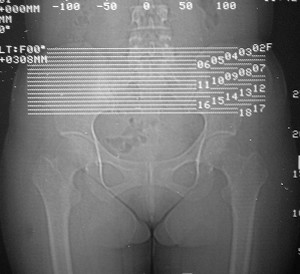

标题: CT7246: F,30岁,下腰痛,同事的片子,请老师们看看,初 [打印本页]

标题: CT7246: F,30岁,下腰痛,同事的片子,请老师们看看,初

典型的致密性髂骨炎

典型的双侧骶髂关节致密性骨炎.

何谓髂骨致密性骨炎?髂骨致密性骨炎是发生于髂骨耳状关节部分的骨质密度增高性疾病。病因迄今不明,可能与妊娠、机械性劳损、病灶性炎症有关。本病好发于20~35岁的育龄妇女,偶见男性。

髂骨致密性骨炎的临床表现与体征:腰骶部疼痛,多呈慢性、间歇性酸痛、隐痛,可向一侧或双侧臀部及大腿后侧扩散,但不沿坐骨神经方向放射,步行、站立、负重及劳累后加重,咳嗽、打喷嚏不能使疼痛明显加重,休息后症状减轻。患者腰骶角加大,局部有压痛和肌紧张,骨盆分离和挤压试验阳性,“4”字试验阳性,化验检查多在正常范围内。x线检查,骶髂关节间隙整齐清晰,靠近骶髂关节面中的髂骨耳状关节部分骨质密度增高,呈均匀浓白边缘清晰的骨质致密带,骨小梁消失,无骨质破坏。本病应注意与早期强直性脊柱炎、骶髂关节结核相鉴别。